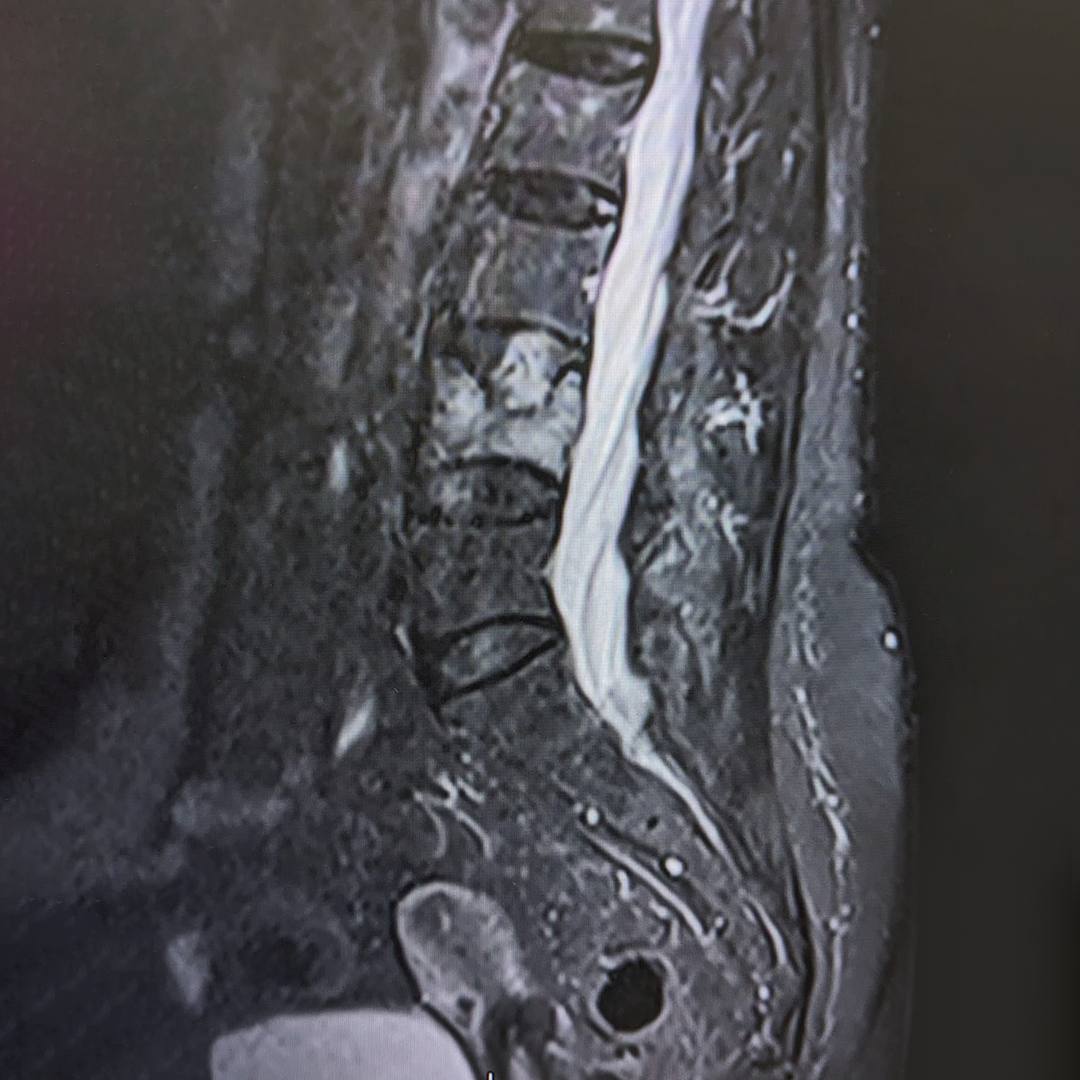

При магнитно-резонансной томографии был выявлен перелом четвертого поясничного позвонка на фоне мягкотканого образования в теле позвонка, вследствие чего пациентке было предложено выполнить дообследование в виде компьютерной томографии.

По результатам КТ и МРТ было заподозрено наличие агрессивной гемангиомы или плазмоцитомы позвонка как причины перелома.

Была проведена биопсия образования в позвонке. По результатам выставлен диагноз злокачественной опухоли – плазмоцитома.